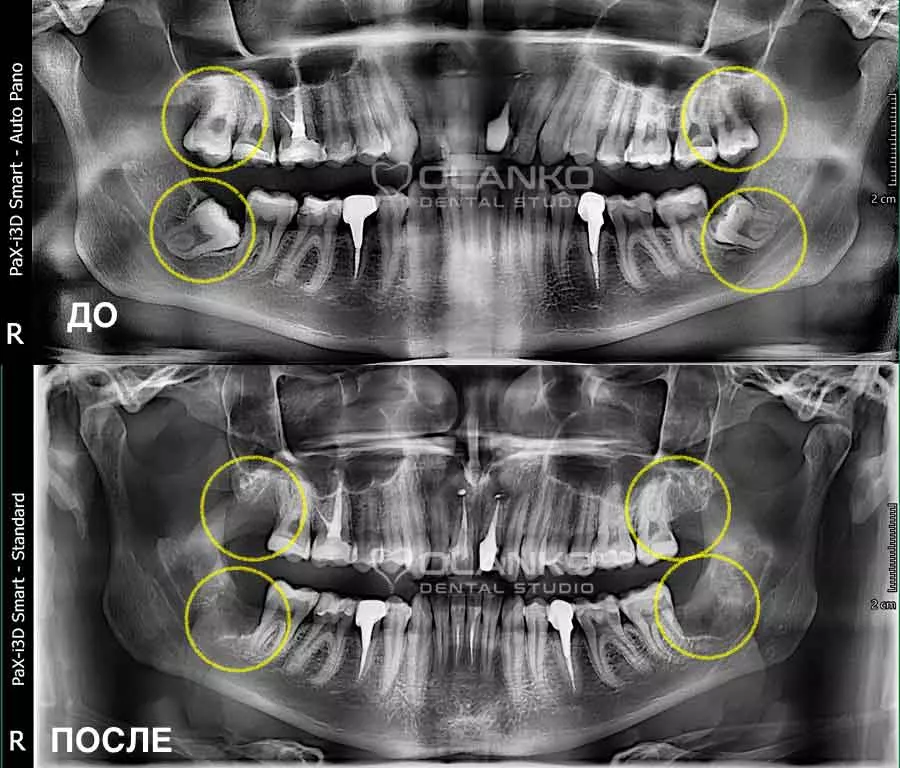

Фото рентген до и после удаления ретенированного зуба мудрости

Фото рентген до и после удаления зуба мудрости Оланко Бровары Киев

Фото панорамный снимок зубов ДО и ПОСЛЕ удаления четырёх зубов мудрости

Фото зуба мудрости после удаления Оланко Бровары Киев